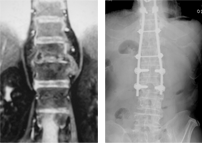

척추 후만증

척추 후만증 수술 전/후 X-ray

수술 전

수술 후

골다공증성 척추골절에 시행한 척추성형술

골다공증성 척추골절에 시행한 척추성형술 수술 전/후 X-ray